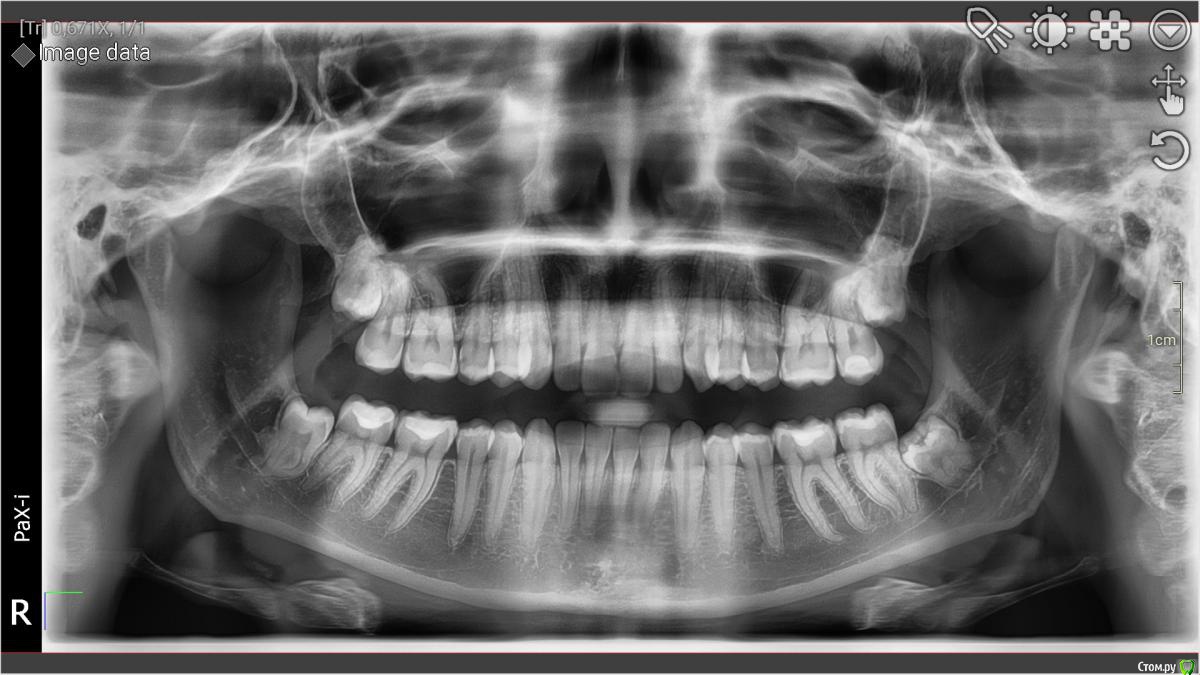

annants Опубликовано 18 февраля, 2019 Поделиться Опубликовано 18 февраля, 2019 Добрый день, уважаемые доктора! Имеется глубокий кариес и скрученность зубов 11 и 21, в связи с чем необходимо подобрать оптимальный метод лечения. Прошу дать совет, как лучше поступить в данной ситуации:композитные виниры или просто реставрация? Керамические виниры, к сожалению, сейчас нет возможности поставить, а зубы лечить нужно. В первую очередь,конечно, необходимо вылечить кариес, но также хотелось бы улучшения эстетического вида. Возможно есть ещё какой-то метод решения проблемы без ортодонтического лечения? Заранее спасибо! Ссылка на комментарий